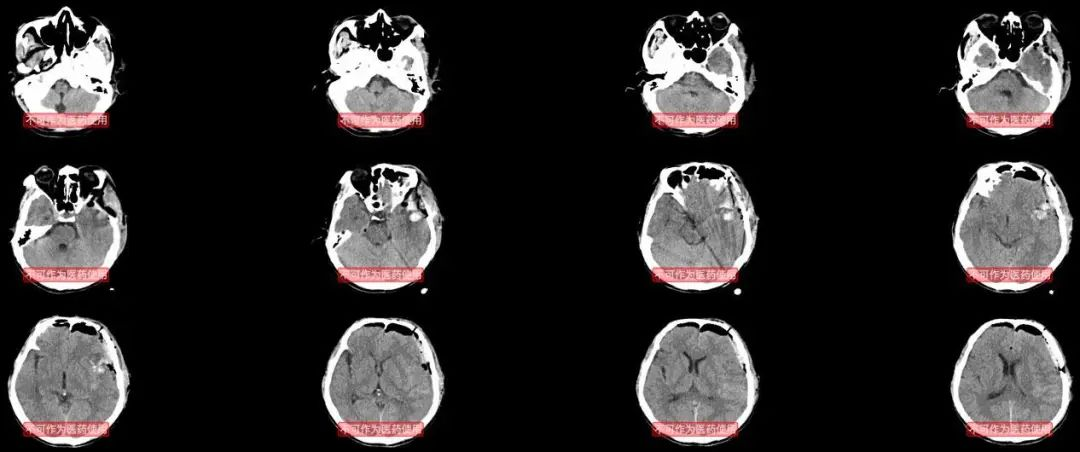

心里还是不放心,因为次日8点需要去机场,早上6点就让住院医生带病人去做头颅CT,心里想,如果需要手术,就不能前往兰州开会,毕竟病人的生命更重要。幸运的是头颅CT还比较理想,没有明显的脑水肿,出血没有增加。病人继续在监护室观察。

术后次日凌晨的CT